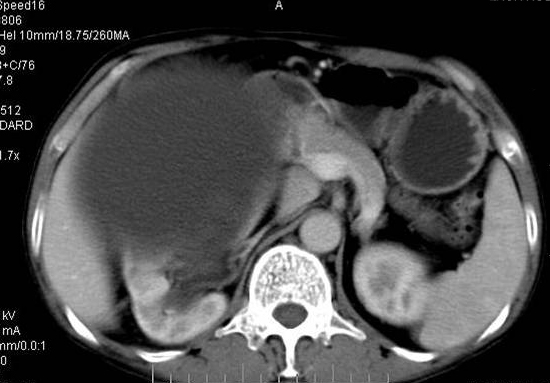

男性 60岁,腹部肿块4年余,肿块逐渐增大,活动性差,无血尿。

门脉期

右肾脏巨大囊样影、囊壁有钙化,囊样影轻度强化有软组织成份。不除外畸胎瘤可能。

巨大囊性肿块,囊壁较厚有强化,有团片状钙化,病灶内下方灶内见片絮状高密度影,增强有轻中度强化,考虑囊性肾癌可能性大

右肾上部巨大的囊实性影,实性部分轻度强化。壁有钙化。考虑右肾囊腺癌。右肾盂积水。